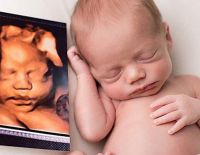

Siêu âm 4D tuần 22 mang lại những lợi ích gì cho mẹ và con?

Siêu âm 4D tuần 22 là một trong những mốc kiểm tra thai rất quan trọng mà mẹ bầu cần ghi nhớ và thực hiện. Để biết siêu âm thai 4D ở tuần 22 mang lại những lợi ích gì, có ý nghĩa như thế...